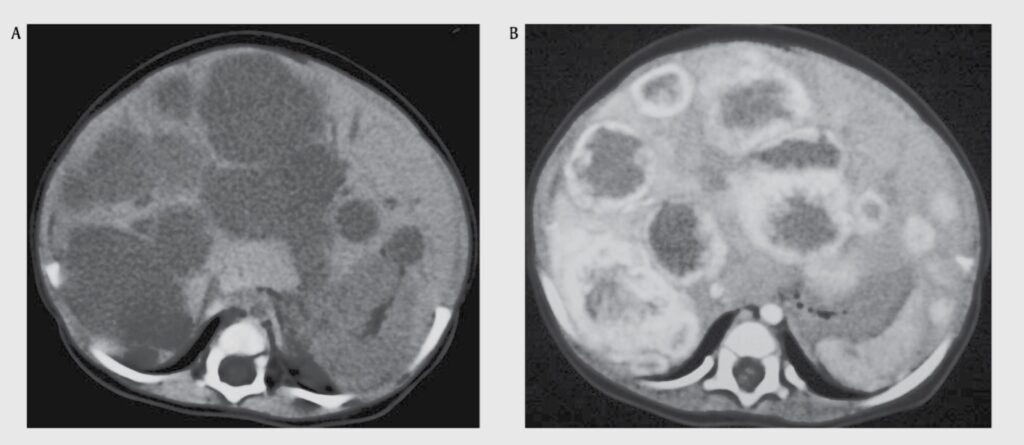

Компьютерная томография с контрастированием органов брюшной полости. На снимках определяются множественные патологические очаги в паренхиме печени. Изображение из книги Vascular anomalies. Mulliken and Young’s.